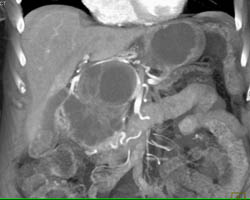

Diagnosis

Cystadenoma